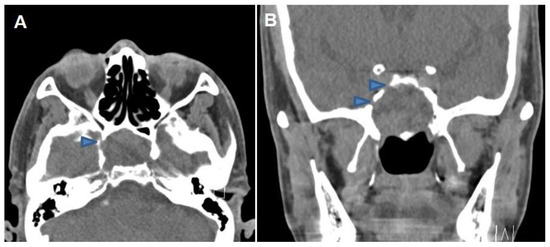

Successful Endoscopic Transsphenoidal Approach Treatment of Sphenoid Sinus Organized Hematoma Causing Visual Deficit: A Case Report

Background: Organized hematoma in the sphenoid sinus is rare, but serious complications, such as visual deficits, can occur. Three such case reports have been published previously in the literature; however, none have achieved complete recovery of the vision. Case presentation: A [...] Read more.

Background: Organized hematoma in the sphenoid sinus is rare, but serious complications, such as visual deficits, can occur. Three such case reports have been published previously in the literature; however, none have achieved complete recovery of the vision. Case presentation: A 69-year-old male patient was referred to the ear, nose, and throat department with an expansile soft tissue mass filling the right sphenoid sinus and blurry vision in his right eye. Complete mass removal was achieved by a wide opening of the sphenoid sinus via an endoscopic transsphenoidal approach, followed by cauterization of the feeding artery and coverage by a nasoseptal flap. The patient’s vision was restored after the operation, and he declared no visual symptoms until the latest follow-up (one year after the surgery). Conclusions: Complete excision with an endoscopic endonasal transsphenoidal approach can restore visual deterioration caused by a sphenoid sinus organized hematoma. Full article